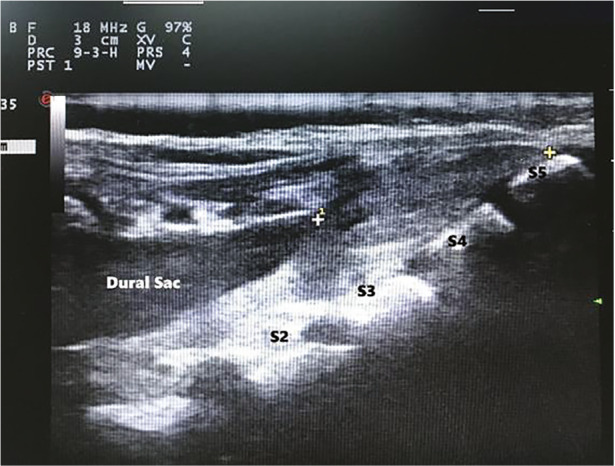

Methods: This study included 348 children aged 1 to 84 months, who were divided into three age groups: 1-24 months, 25-48 months, and 49-84 months. Sacral cornua were assessed using both palpation and ultrasound imaging. Palpation findings were categorized as "good", "difficult", or "non-palpable". Ultrasound imaging of the sacral cornua was classified as "clear", "unclear", or "invisible". Measurements taken included the inter-cornual distance, the anteroposterior diameter of the sacral canal, the distance from the skin to the sacral canal, and the distance from the dural sac to the cornua level.

Results: Palpation of the sacral cornua was rated as "good" in 75.9% of patients, "difficult" in 22.4%, and "non-palpable" in 1.7%. All patients with "good" cornua palpation were also classified as "clear" on ultrasound imaging. Among the cases with "difficult" palpation, 76% showed a "clear" ultrasound image, while 24% were "unclear". Only one patient had "invisible" cornua on ultrasound. The mean distance from the dural sac to the cornua level was 3.72±1.64 cm, and this distance increased significantly with age (P < 0.01).

Conclusion: Ultrasound is a valuable tool for identifying the sacral cornua, especially when palpation is difficult, and offers reliable, detailed information on sacral anatomy.